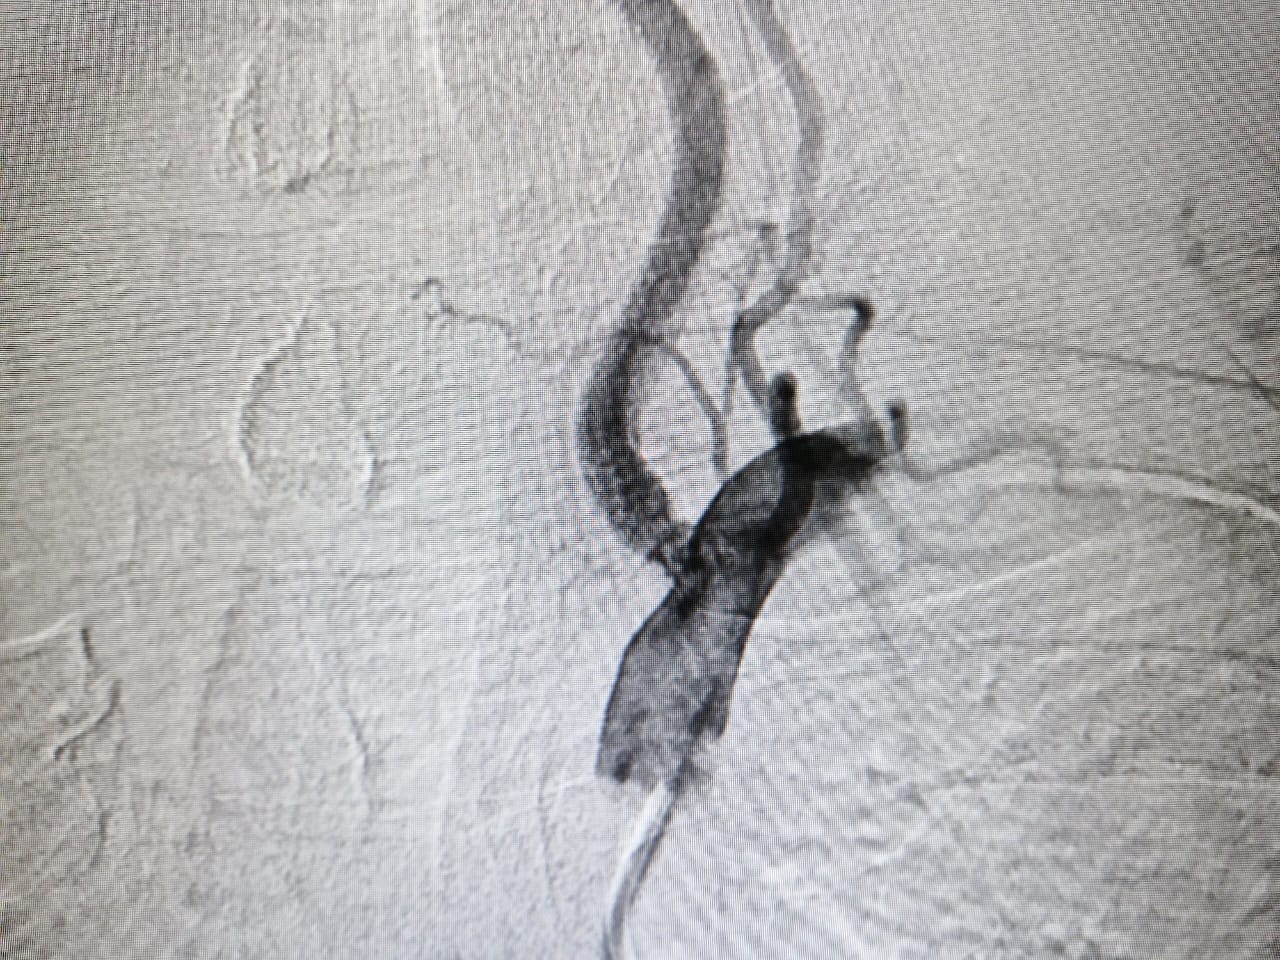

विगत दिवस भिंड निवासी 60 वर्षीय मरीज जिसको स्ट्रोक हुआ था, बीआईएमआर हॉस्पिटल में आया बीआईएमआर हॉस्पिटल के वरिष्ठ न्यूरोलॉजिस्ट एवं स्ट्रोक स्पेशलिस्ट डॉ. सौरभ गुप्ता ने मरीज को देखा और तुरंत ही उनकी एमआरआई कराई, जिसमें की मरीज के मस्तिष्क में स्ट्रोक का होना पाया गया डॉ. सौरभ गुप्ता ने तुरंत ही मरीज का डीएसए (मस्तिष्क एंजियोग्राफी) किया जिसमें उसके बाएं कशेरुका (वर्टेब्रल) धमनी में बाधा (95% स्टेनोसिस) था। संभावना थी कि यदि इलाज नहीं किया जाता है तो धमनी का पूरा रुकावट हो सकता है और रोगी को दूसरा स्ट्रोक हो सकता है। गंभीरता को देखते हुए डॉक्टर ने अत्याधुनिक न्यूरोइंटरवेंशन तकनीक की मदद से मरीज के मस्तिष्क की पिछली धमनी में Stenting की गई । ऑपरेशन के दौरान रोगी की न्यूरोलॉजिकल स्थिति की निगरानी रखने के लिए रोगी को जागृत रखा गया व ऑपरेशन के दौरान डॉक्टर लगातार मरीज से बात करते रहे ।

यह एक कठिन ऑपरेशन था क्योंकि मस्तिष्क की पीछे की धमनियां पतली कैलिबर की होती हैं और उनकी पहुंच मुश्किल होती है।